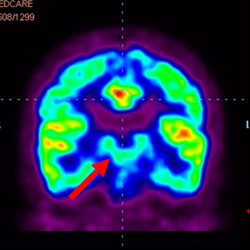

細(xì)胞治療前 PET CT 掃描顯示神經(jīng)組織中的藍(lán)/黑色區(qū)域,表明腦癱引起的大腦損傷。

細(xì)胞治療后,藍(lán)色和黑色區(qū)域減少,并且看到更活躍的區(qū)域。這表明損傷減少并改善了大腦功能。

這證明細(xì)胞療法是治療腦癱兒童安全有效的方法。細(xì)胞療法可以更新大腦損傷的核心,并且可以通過 PET CT 掃描來監(jiān)測大腦的改善情況。這些細(xì)胞療法與標(biāo)準(zhǔn)治療一起促進(jìn)腦癱兒童的生長和改善。